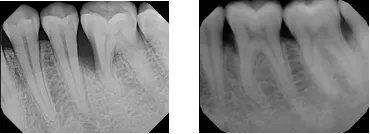

Before & After

Note: Patients depicted in photos have provided their consent to display their pictures online. Results may vary.